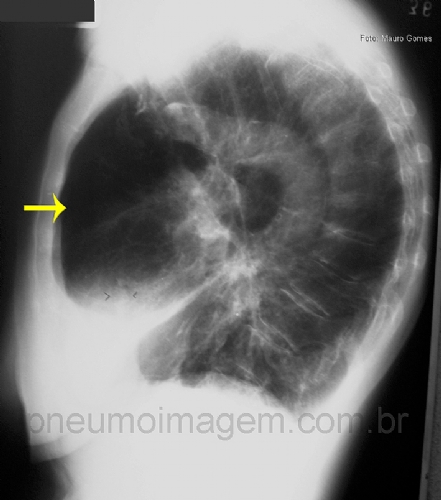

Veja imagens de DPOC no PneumoImagem,

clicando aqui.